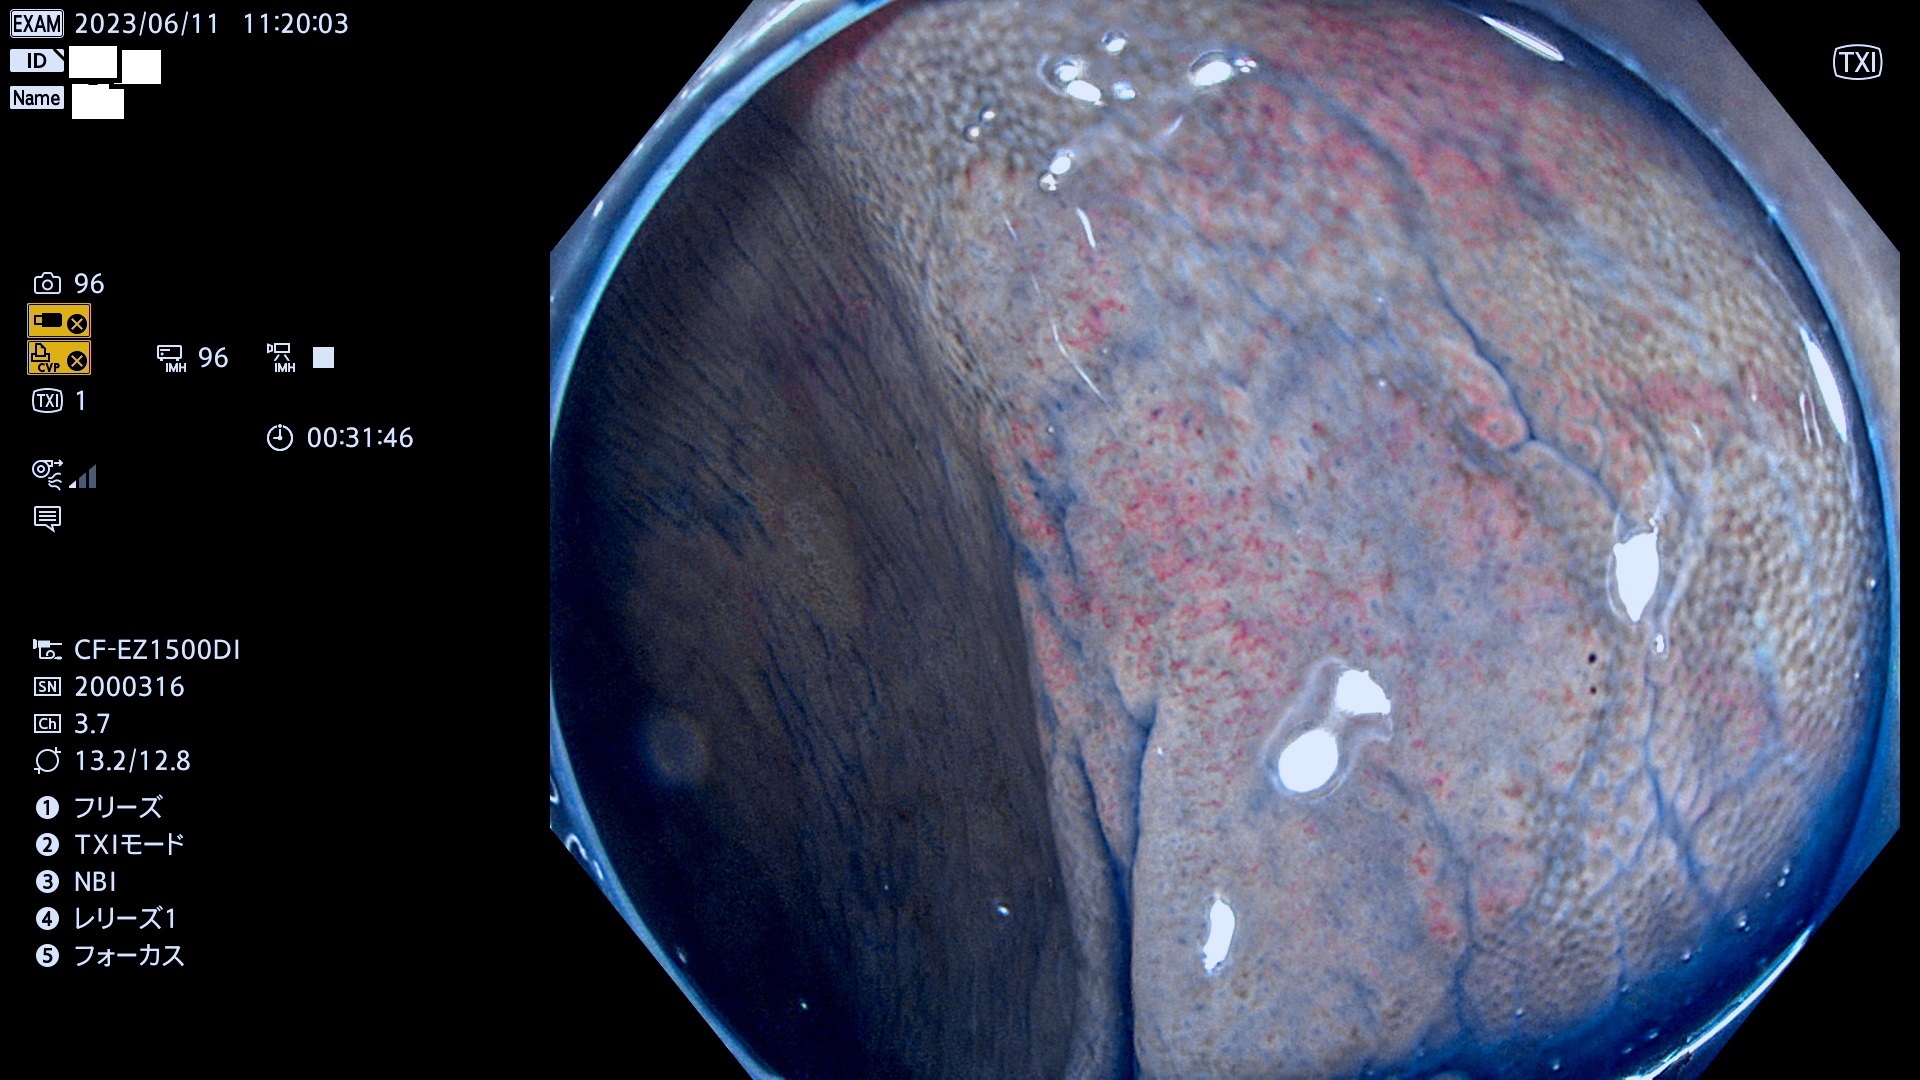

「表面型腫瘍」の中で、完全に平坦な物をUb、陥凹している物をUcと呼びます。平坦隆起型(Ua)よりも、発見が難しく危険な病変です。このタイプの発見率は「腺腫発見率」よりも、遥かに重要な意義があります。

毎週の検査(木・金・土・日)に当院の検査で発見されたUb、Uc病変を、その週の日曜の夜にUPし1週間、提示します。

抽出の対象期間 2023年6月8日(木)〜11(日)の4日間(48件の検査)